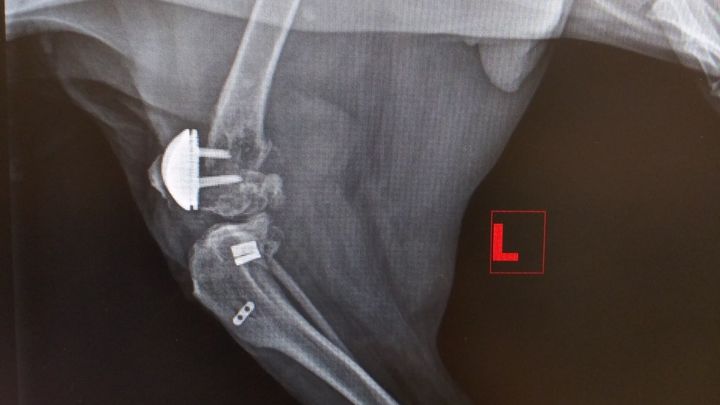

I wanted to start by saying Im sorry Ive been MIA. The flu & pink eye has made their rounds with meh human family, yuck! Thankfully everyone is almost back to 100%! Sad news today from meh vet *sigh* looong story short Im not using meh back L leg at all. Meh pawesome vet noticed this & that its super swollen so he did some xrays. Meh right is a ok. My L as you may be able to see looks like it exploded He sent the xrays to the surgeon who did meh patella replacements to see what he thinks needs to be done. At best & at the very least all the hardware has to be removed & set the femur. At worst I could loose meh leg. So moms waiting to hear from meh vet after he talks to the surgeon to get our game plan. Got a pain shot & sent home with meds & an antibiotic. Regardless of what I need done we need money to do it before I can get fixed, if anyone can help me I would be so grateful ❤